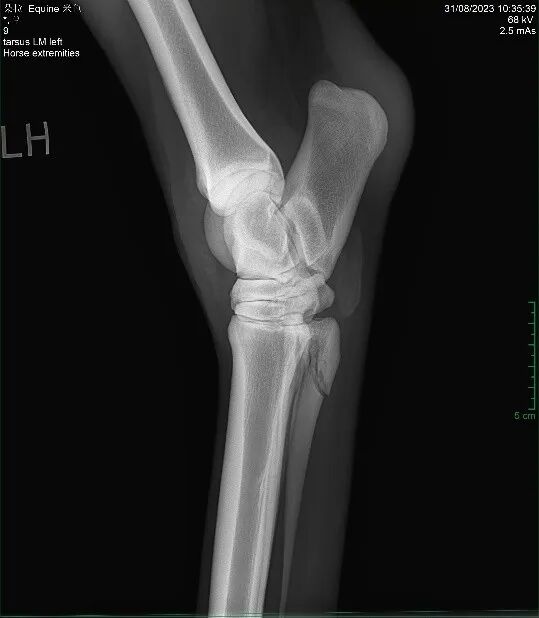

踢伤造成的马第四跖骨骨折。由于该处不直接负重、较稳定,一般休养3个月左右即可。 图源:王炜晗